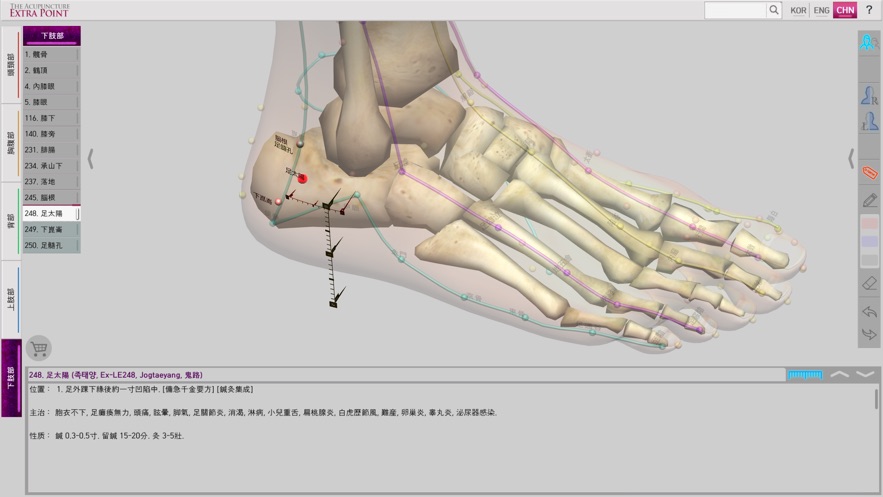

‘The Acupuncture of Extra Point’ was created by integrating Extra Point from the past, and the newly discovered New Point together as one product. It allows for easy comparison because it expresses 14 Main Acupuncture Point Meridian and the Extra Acupuncture Point together in a male and female 3D model. Easily zoom in and out with multi-touch so you can see the exact location of The Acupuncture Point. It is recommended for people who want to see both 14 Main Acupuncture Point Meridian and the Extra Acupuncture Point at the same time. Contents include accurate location, based book, function and character (how to use). Released in Korean, Chinese and English, which allows it to be used across the world! With realistic skin, bone, and internal organs in 3D human body model, everything is distinguished by rich colors so it is very easy to see. It is based on The International Standard Acupuncture Points of WHO, WHO`s International Standard Terminologies on Traditional Medicine in The Western Pacific Region, The acupuncture textbooks of the university of Asian Medicine and 'Huangdi Neijing - Lingshu’. It is supervised by professors and Korean medical doctors from Korea Medical University. * 14 Main Acupuncture Point Meridian - 12 Main Acupuncture Point, Governor Vessel (GV) Acupuncture Point, Conception Vessel(CV) Acupuncture Point.- See The Meridian 2.0

‘The Acupuncture of Extra Point’ is the only product in the world that expresses the Extra Acupuncture Point on male and female 3D human models.

‘The Acupuncture of Extra Point’ is easy to use because it displays The Extra Acupuncture Point on 3D human body model. As well, the Extra Acupuncture Point and 14 Main Acupuncture Point Meridians are displayed together with the accuracy, so you can easily compare.

In 'The Acupuncture of Extra Point’, the skin, bones, and internal organs of the 3D human model look realistic. The 14 Main Acupuncture Point Meridians and the Extra Acupuncture Point are distinguished by rich colors so they are very easy to see.

The contents of 'The Acupuncture of Extra Point’ was created in Korean, Chinese and English together, which allows it to be used across the world!